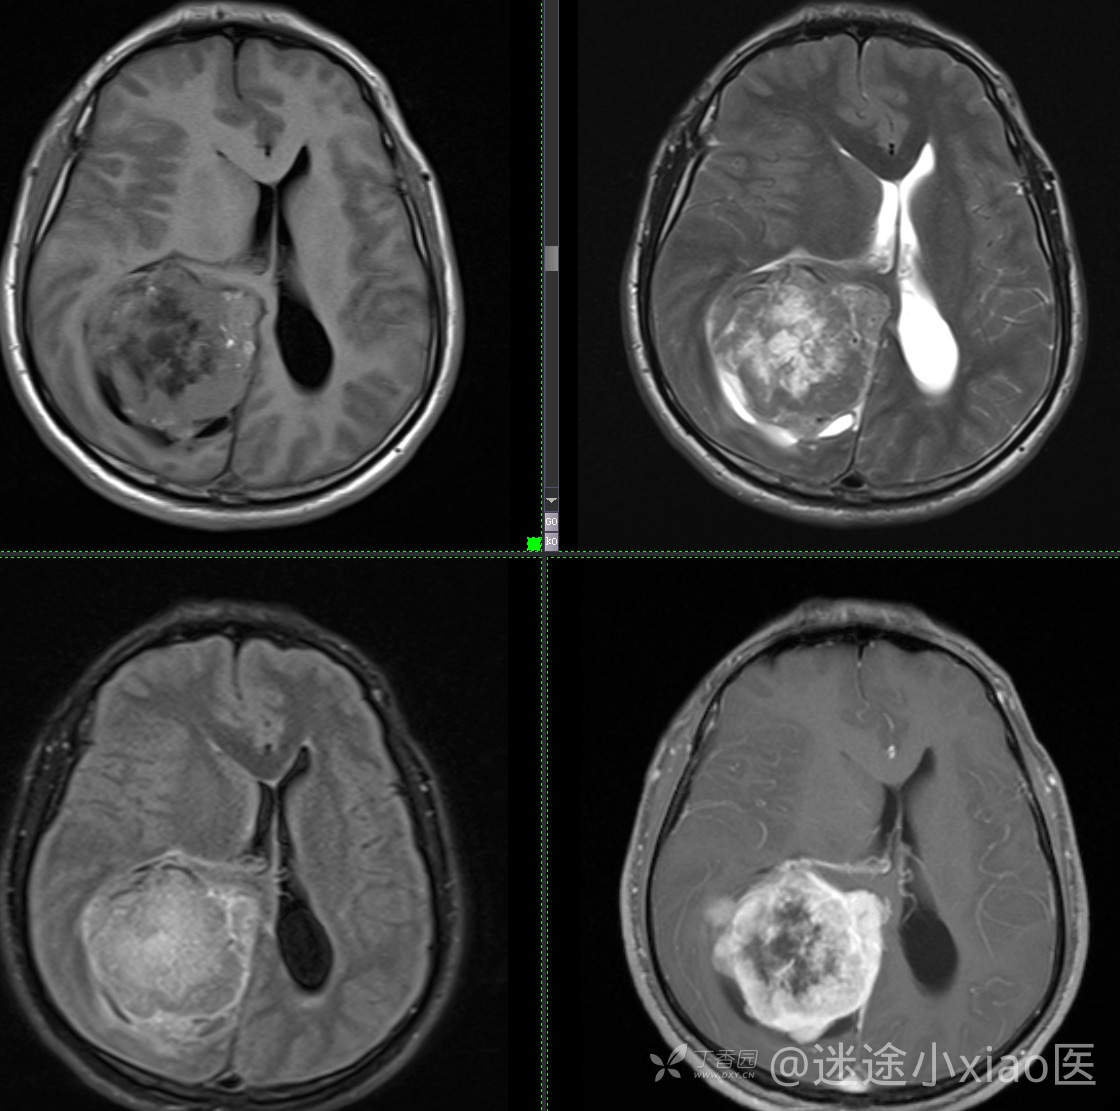

患者年龄:43

患者性别:男

简要病史:头痛3月余,查体无殊